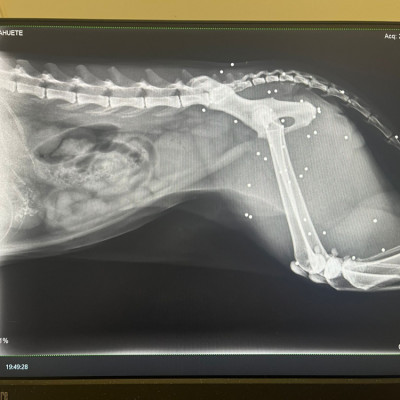

Lo rescatamos desde Francia, y, al llegar aquí, nos encontramos con este panorama desolador para él:  una auténtica barbaridad de perdigones en el cuerpo y una cardiopatía ❤️‍🩹 Las imágenes hablan por sí solas...